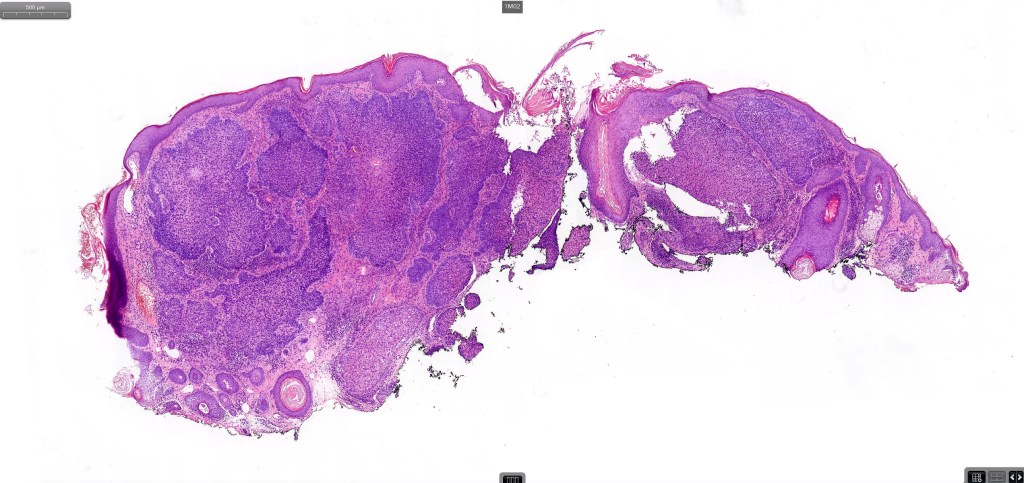

•Both epithelial & fibrous stromal components

•The tumor commonly arises from the epidermis

•The epithelial component is composed of uniform small, basophilic devoid of desmosomes

•Peripheral palisading

•A wide variety of histological variants are possible including nodular, nodulocystic, ulcerative, superficial, micronodular, infiltrating/infiltrative, keratotic, basosquamous, pigmented, morpheaform, keloidal, clear-cell, signet-ring cell & granular cell variants, BCC with monster cells, BCC with metaplastic features, BCC with matricial differentiation, basomelanocytic tumor (see separate blog), BCC with thickened basement membrane, BCC with carcinoid-like nuclear palisading & these are illustrated below